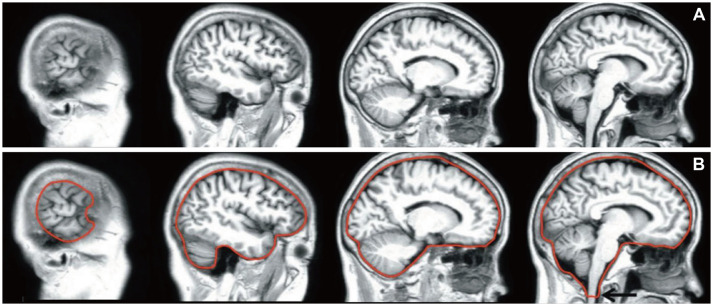

结构磁共振成像(sMRI)通过提供高分辨率的解剖信息,在神经系统疾病的评估中发挥着关键作用。定量后处理技术的最新进展通过检测与各种神经和精神疾病相关的细微形态学变化,扩大了sMRI的应用范围,超出了视觉评估。本文综述了目前基于smri的分析的临床应用,包括脑容量测量、形状分析、基于体素的形态测量(VBM)、基于表面的形态测量、基于源的形态测量和基于体素的病变症状制图(VLSM)。基于体积和形状的分析允许评估区域特异性萎缩和分区域形态改变,而基于VBM和基于表面的形态测量提供了对组织体积和皮质表面结构的补充见解。基于源的形态测量揭示了结构协方差的网络水平模式,VLSM直接将病变位置与功能结果联系起来,特别是在中风中。已经证明,这些方法在阿尔茨海默病、帕金森病、多发性硬化症、癫痫和重度抑郁症等疾病中具有临床相关性。通过量化传统成像方法难以检测到的大脑结构改变,这些工具提高了诊断准确性,支持预测,并促进了治疗效果的监测。这篇综述强调了sMRI后处理技术日益融入临床神经病学。

Structural magnetic resonance imaging (sMRI) plays a pivotal role in the evaluation of neurological disorders by providing high-resolution anatomical information. Recent advances in quantitative postprocessing techniques have expanded the utility of sMRI beyond visual assessments by enabling the detection of subtle morphological changes associated with various neurological and psychiatric conditions. This review summarizes current clinical applications of sMRI-based analysis, including brain volumetry, shape analysis, voxel-based morphometry (VBM), surface-based morphometry, source-based morphometry, and voxel-based lesion-symptom mapping (VLSM). Volumetric and shape-based analyses allow for assessments of region-specific atrophy and subregional morphological alterations, while VBM and surface-based morphometry provide complementary insights into tissue volumes and the architecture of the cortical surface. Source-based morphometry reveals network-level patterns of structural covariance, and VLSM directly correlates lesion locations with functional outcomes, particularly in stroke. It has been demonstrated that these methodologies are clinically relevant in conditions such as Alzheimer's disease, Parkinson's disease, multiple sclerosis, epilepsy, and major depressive disorder. By quantifying structural brain alterations that are not readily detectable using conventional imaging methods, these tools improve diagnostic accuracy, support prognostication, and facilitate monitoring of treatment effects. This review highlights the growing integration of sMRI postprocessing techniques into clinical neurology.